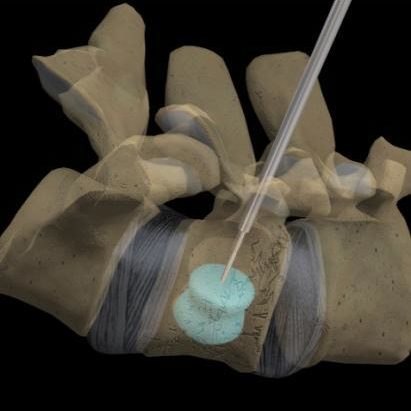

Back surgery might be an option if conservative treatments haven't worked and your pain is persistent and disabling. They are very well tolerated by the dental tissues. Your surgeon puts cement into your broken bones to help keep your spine stable.

Compression of spinal nerves caused by arthritis or scoliosis vertebroplasty, which is the injection of bone cement into compressed vertebrae. A couple of months later i developed terrible back pain after getting into a chair to have my eyebrows done. Thanks to new and innovative techniques there has been a revolution in back and neck surgery. 41:30 the frcs mentor 3 612 просмотров.